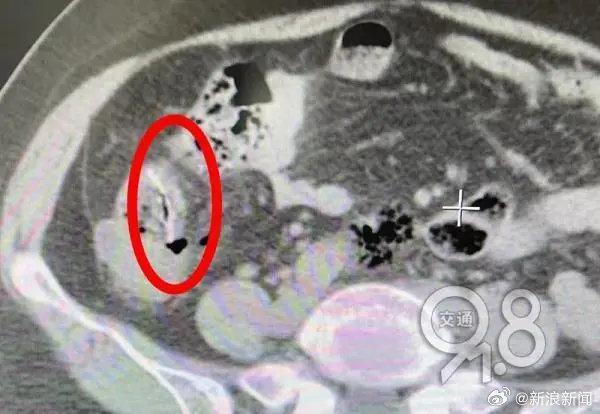

10月底,胡大姐边吃鱼边聊天,一根大的鱼刺卡在喉咙,她连吞几口米饭,把鱼刺咽了下去。第二天她开始有腹痛,到第四天,因疼痛难忍被送到杭州市一医院急诊。该院胃肠肛外科毛宗磊医师查体发现她腹部压痛、反跳痛明显,肚子僵硬,血液检查显示白细胞严重超标,是腹膜炎的信号。腹部CT发现,胡大姐的小肠腔内有条状异物。综合患者描述,医生判断其体内异物就是鱼刺,安排腹腔镜探查。在术中发现,胡大姐腹腔内已产生大量脓性腹水,回肠部有一根硕大的鱼刺穿破小肠,露出尖头,穿孔处的肠壁及系膜高度水肿。

由于肠穿孔时间较久,发生严重的弥漫性腹膜炎,腔镜已无法解决问题,医生决定转为开腹手术。取出鱼刺后,由于感染太重,无法马上进行小肠吻合,在征得家属同意后,医生进行肠造口,让排泄物从“人工肛门”排出,几个月后再进行二期手术回纳。